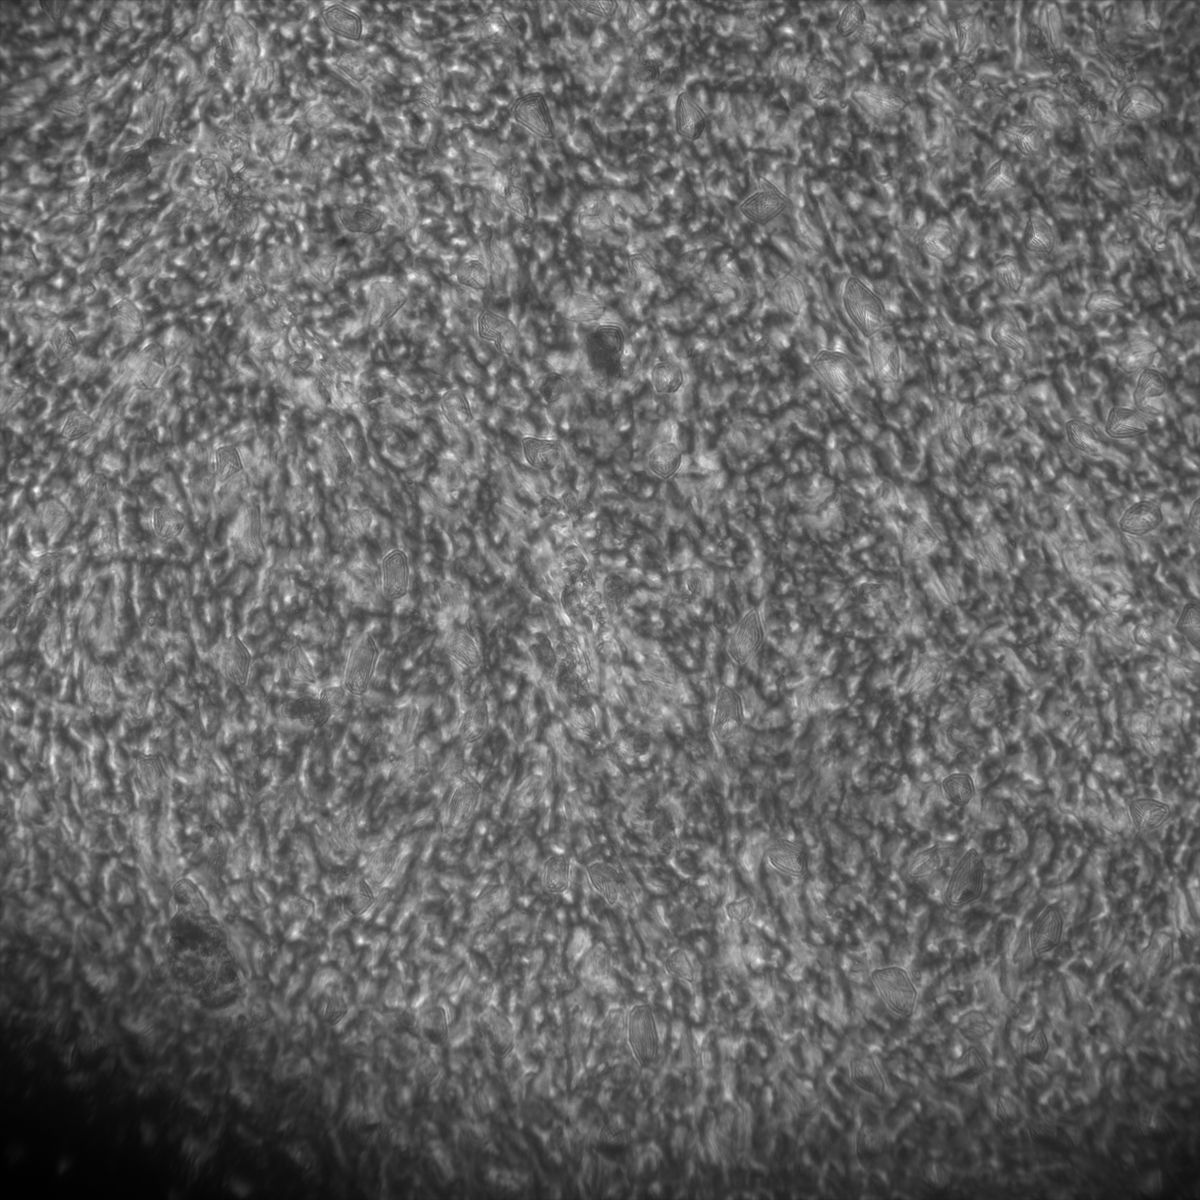

Healthy Eye